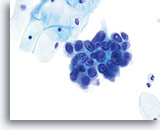

Konventioneller Pap-Abstrich

Adenokarzinom

Konventioneller Pap-Abstrich

Adenokarzinom